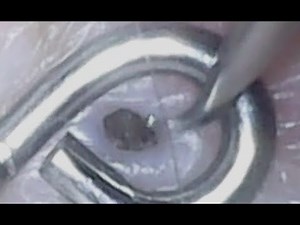

- Pore of Winer

Removal - Dilated Pore of Winer

Chest - Giant Pore of Winer

Pore of Winer - Gigantic

Pore of Winer - Infected

Pore of Winer - Huge Pore of Winer